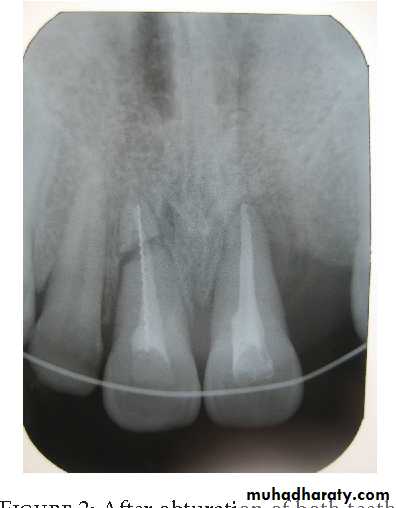

Root end resection:

Root end preparation and restoration:

Root end filling materials: